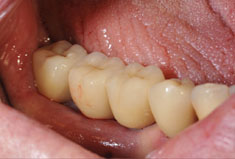

Fehlen in der Front oder im Seitenzahnbereich mehrere Zähne, ist eine Brücke oder Prothese vollkommen unnötig. Die fehlenden Zähne können entweder einzeln durch eine entsprechende Anzahl von Implantaten oder durch implantatgetragene festsitzende Brücken ersetzt werden. Das Bild der Kronen zeigt die drei Verschraubungen deutlich, im Mund liegen diese verdeckt am Gaumen oder im Bereich der Zunge.